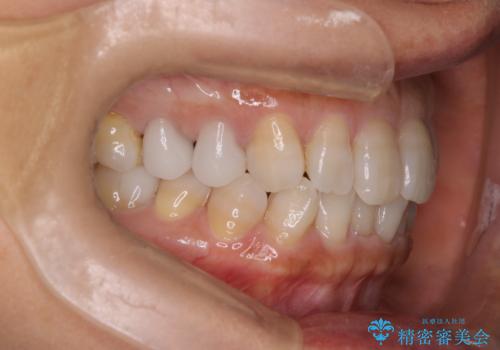

【インビザライン】下前歯だけを治したい

- 50代女性

- 矯正装置

- インビザライン

- 治療期間

- 8ヶ月

- 下前歯のがたつきにより唇を巻き込んでかんでしまい痛いため矯正をしたいという主訴で来院されました。今回は下顎前歯のみという強い希望があり、下顎のみのインビザライン矯正をしました。

叢生を改善するためのスペースはIPRと拡大を行いました。治療後は唇を巻き込んでしまう主訴が改善し、ご満足していただけました。